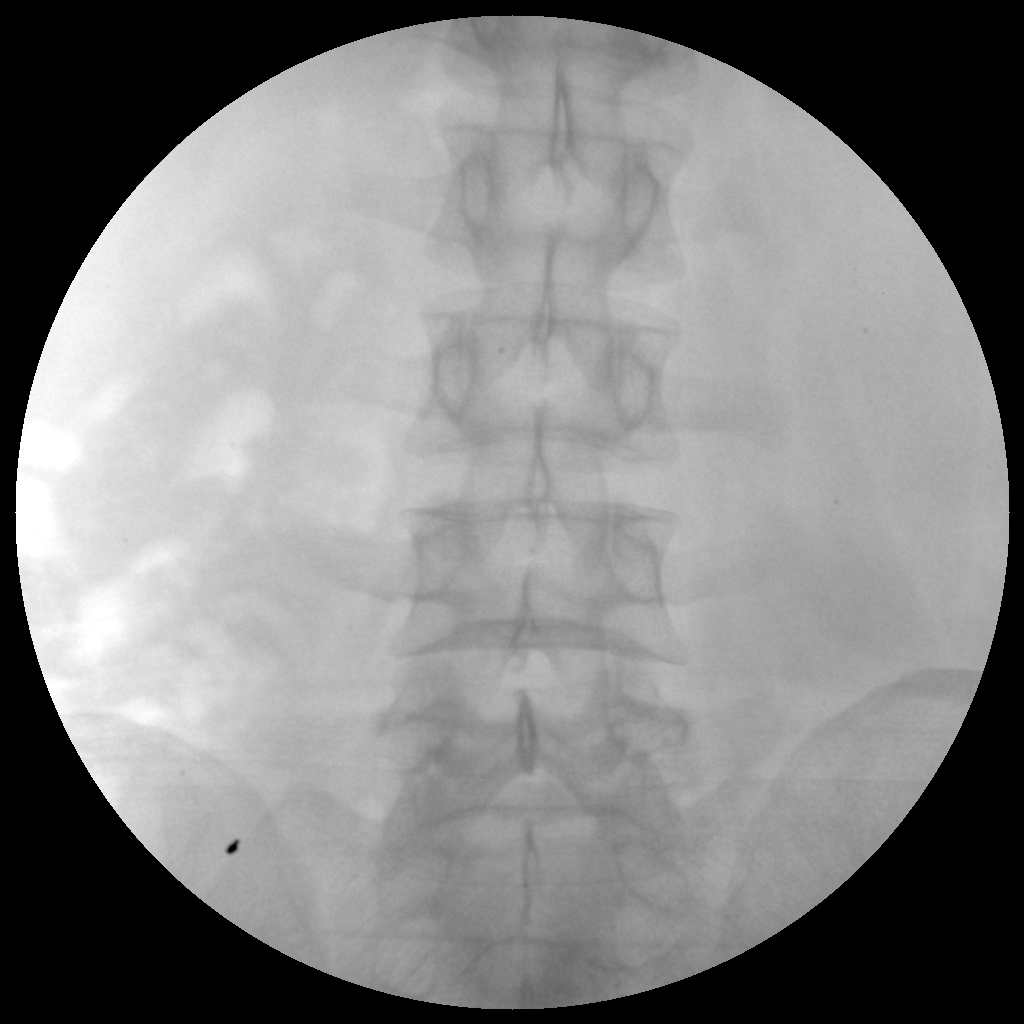

●全數(shù)字化百萬(wàn)像素影像系統(tǒng),圖像清晰